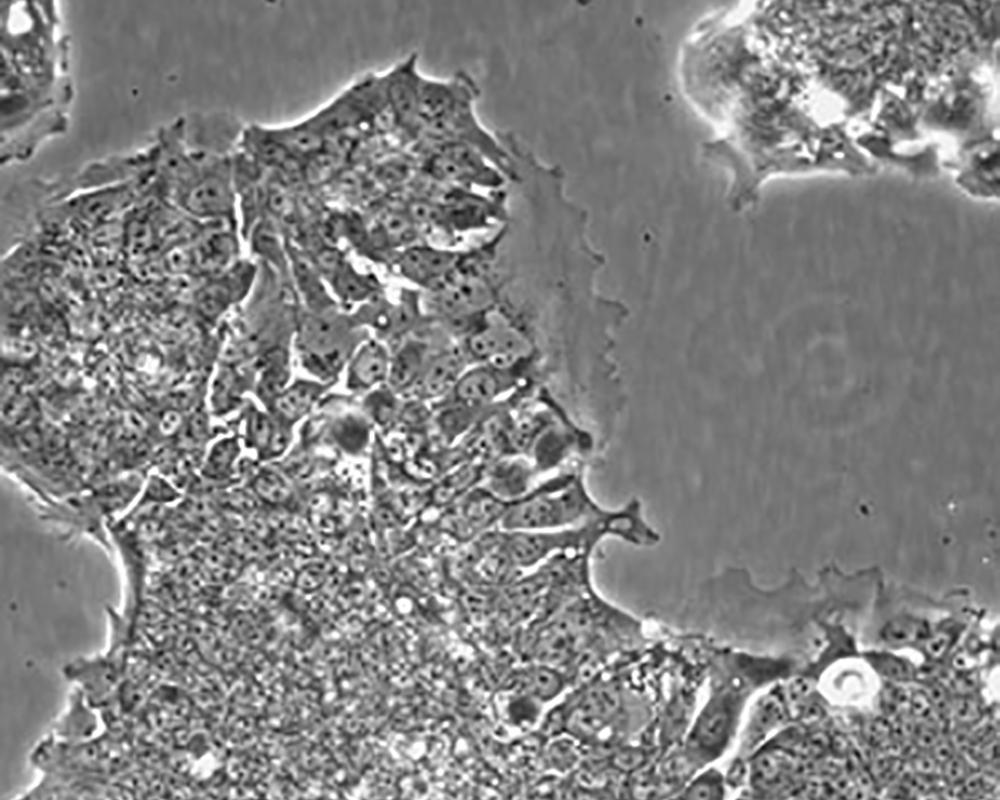

形態(tài)特征 epithelial

細(xì)胞描述 T84細(xì)胞株是從一位72歲男性結(jié)腸癌患者的肺轉(zhuǎn)移灶建立的可移植人類癌細(xì)胞株。 腫瘤組織皮下接種于BALB/c裸鼠,并連續(xù)進(jìn)行移植。 [26072] 在裸鼠身上的移植過程中,細(xì)胞株始終保持結(jié)腸癌的原始組織性狀。 [26072] 在無胸腺小鼠中傳代23代后建立了T84細(xì)胞株。 這些細(xì)胞單層生長到飽和并在接觸細(xì)胞間展現(xiàn)出緊密連接和橋粒。 [1155] 有很多關(guān)于多肽類激素和神經(jīng)遞質(zhì)并維持定向電解質(zhì)傳輸?shù)氖荏w。 [1155] 這株細(xì)胞展現(xiàn)了接觸細(xì)胞中的緊密連接和橋粒。 [1155] 角蛋白免疫過氧化物酶染色陽性。